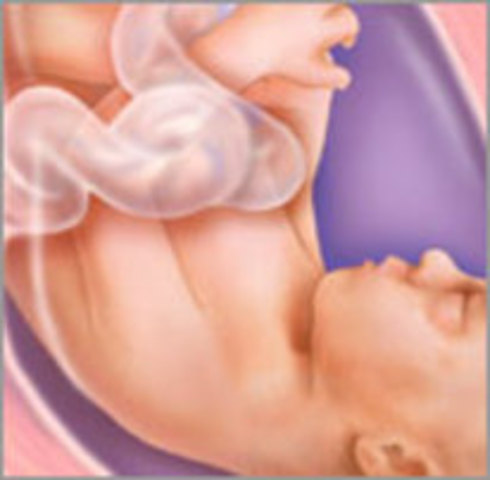

• Week 24

Week 24

His skin is still thin and translucent, but that will start to change soon.